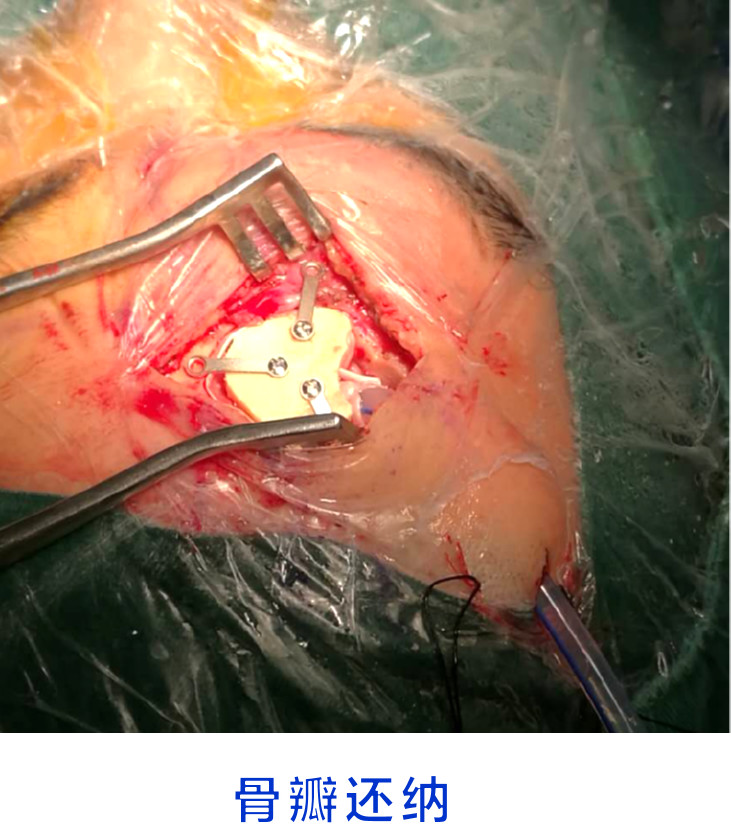

诊疗经过

术后